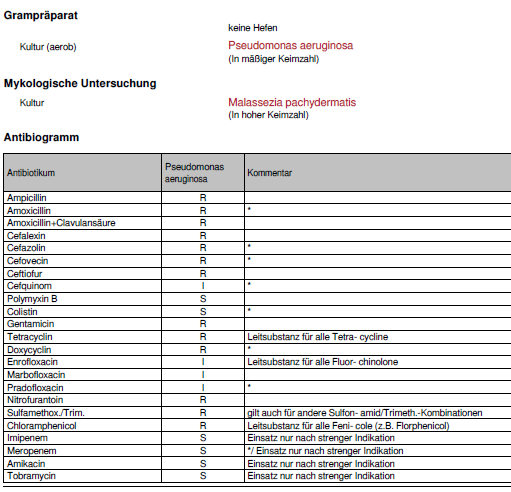

In nebenstehendem Befund kann man einen Problemkeim erkennen. Es ist Pseudomonas aeruginosa mit einer Multiresistenz. Nur noch wenige Antibiotika sind wirksam. Imipenem, Meropenem, Amikain und Tobramycin sind “Panzerschrankantibiotika” aus der Humanmedizin, die wir bei Tieren im Angesicht der MRSA-Infektionen des Menschen keinesfalls einsetzen dürfen. in jedem Fall müssen wir eine neue Strategie gegen den Keim entwickeln. In neuerer Zeit nimmt der begriff “Biofilm” gerade in der Kombination Ohrentzündung und Pseudomonas eine zunehmende Bedeutung ein. Nimmt man diesem Biofilm im Ohr seine Grundlage, kann man auch Erfolg trotz Multiresistenz haben

Otiprin: Chloramphenicol, Dexa, DMSO, Benzoylbenzoat.

Aurizon: Marbofloxacin, Dexa, Clotriamzol.

Surolan: Polymixin B, Miconazol, Prednisolon

Easotic: Gentamycin, Hydrocortison, Miconazol.

Otomax: Gentamycin, Betamethason, Clotrimazol

Oribiotic: Neomycin, Nystatin, Triamcinolon.

Posatex: Orbifloxacin, Mometason, Posaconazol

Osurnia: Terbinafinum, Florfenicol, Betamethasonacetat